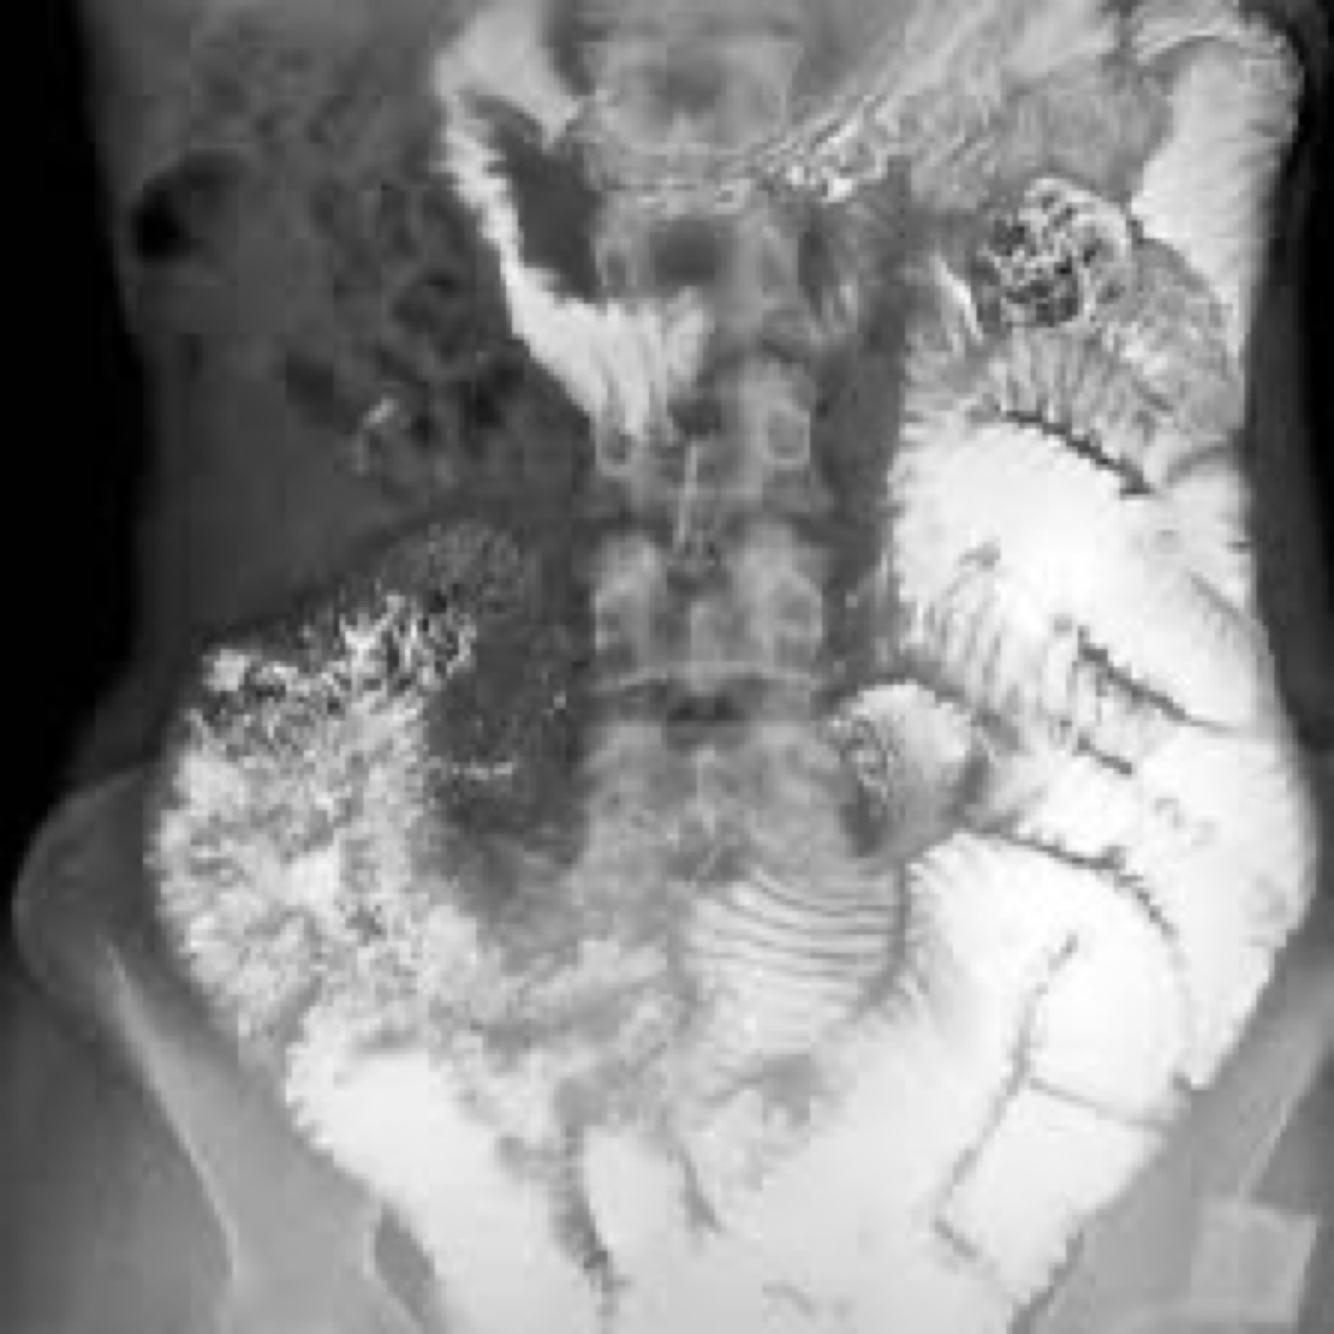

What disease has a barium clumping x- ray?

A

Celiac sprue